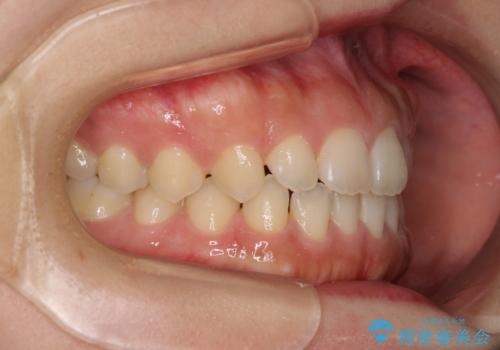

気になる隙間の再矯正 前歯をインビザライン・ライトで改善

- 後戻りによる上下前歯の隙間を気にして来院された患者様です。

歯列不正はそれほど大きくなかったため、インビザライン・ライトを用いて矯正治療を行うこととしました。

無理のないペースで治療を進め、9ヶ月で終えることができました。